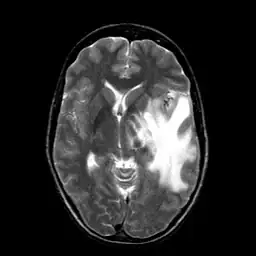

I am currently working on translating Matlab version active contour to OpenCV. It seems that OpenCV has its own version of active contour but deprecated then. I am curious about how different between this version with Matlab version. So I did a comparison experiment. Given a MRI brain image and an initial boundary , I applied both Matlab and OpenCV version active contour to segment the white matter in brain.

For both Matlab and OpenCV, I choose gradient(edge) method of active contour. I then labeled the results on the image. The red curve is initial boundary while the green curve is final boundary.

It seems that Matlab does a really good job when choosing the appropriate parameters. The "ContractionBias" parameter (refer it here) is really useful for controlling the curve to shrink or expand.

However, the OpenCV version active contour seems doesn't work at all. I use slider bar to change the parameters alpha, beta and gamma but cannot get a descend result. It seems that the curve doesn't expand no matter how I set the parameters. I use OpenCV 2.4.13.3 and active contour can be found in legacy folder as snakes.cpp. Chek OpenCV github or more specifically snakes.cpp. The OpenCV test code is: